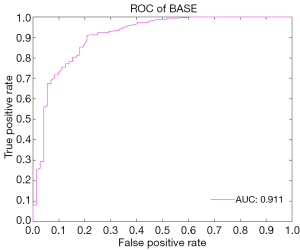

In the external validation, the AUC obtained by the RF algorithm was 0.940, with an accuracy of 0.875, a sensitivity of 0.875, and a specificity of 0.958 (Table 2 and Figure 3B). Furthermore, our best-performing model (i.e., RF algorithm) identified BASE as the most critical parameter for the accurate prediction of postoperative IMH status (Figure 4). To better illustrate the importance of BASE, binary logistic regression analysis was derived for prediction of IMH status using BASE in internal validation set. The ROC curve of BASE was showed in Figure 5, with an AUC of 0.911.

In addition, our best-performing ML model (using RF algorithm) identified that BASE is the most critical feature for the prediction of postoperative IMH status, and a binary logistic regression analyse derived for BASE also presented a well-performed result, with an AUC of 0.911. These findings suggest that the size of IMH may be the most important parameter to determine the postoperative status. Most investigators have assumed that tangential traction to the fovea plays a crucial role in the development of IMH and that the success of IMH surgery is highly dependent on the relief of such traction. BASE, the maximum diameter of IMH at the RPE layer, directly reflects the size of retinal defects in the foveal neurosensory retina. In addition, it serves as an indicator of the transverse traction force to the fovea. Therefore a smaller BASE often means less tractional force, which is more likely to be removed by a standard VILMP surgery. Similarly, a prior study used a binary logistic regression analysis to evaluate the prognosis predictive power of several OCT parameters (e.g., MIN, BASE, MHI), which also showed that BASE is the strongest indicator in predicting anatomical success after IMH surgery (16).